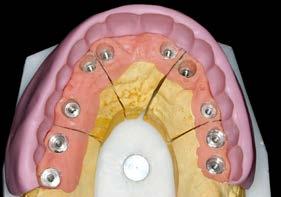

Figura 4. Prótesis de carga progresiva finalizada, lista para su colocación.

5 y 6. Prótesis atornillada de carga progresiva en la fase previa a la confección de la prótesis definitiva.

En el arco superior se planifica una rehabilitación cementada por tramos, que en ese contexto representaba la mejor alternativa en términos de estética y estanqueidad, mediante pilares específicos para fresado. Para ello se programan 10 implantes. En una primera fase se realiza la carga inmediata

del sector anterior y la carga definitiva de los implantes mandibulares mediante una prótesis de resina atornillada (Figura 3).

Seis meses después se cargan los implantes de los sectores posteriores con una prótesis atornillada sobre transepiteliales de larga duración en metal-resina, lo que permite generar una carga controlada y favorecer la adecuada conformación de los tejidos periimplantarios (Figura 4).

Una vez alcanzada la estabilidad de los tejidos blandos, 6 meses después de la carga progresiva se inicia la confección de la prótesis definitiva (Figuras 5 y 6).

El diseño de la prótesis superior se basa en la confección de pilares de oro ceramizado en los sectores anteriores, con el objetivo de optimizar la estética, y biopilares fresables en la zona posterior. Estos pilares permiten una correcta adaptación al perfil gingival y presentan un adecuado grado de estanqueidad, minimizando el riesgo de microfiltraciones que puedan favorecer infecciones periimplantarias. Hace 25 años constituían una de las mejores alternativas estéticas y funcionales para este tipo de rehabilitaciones.